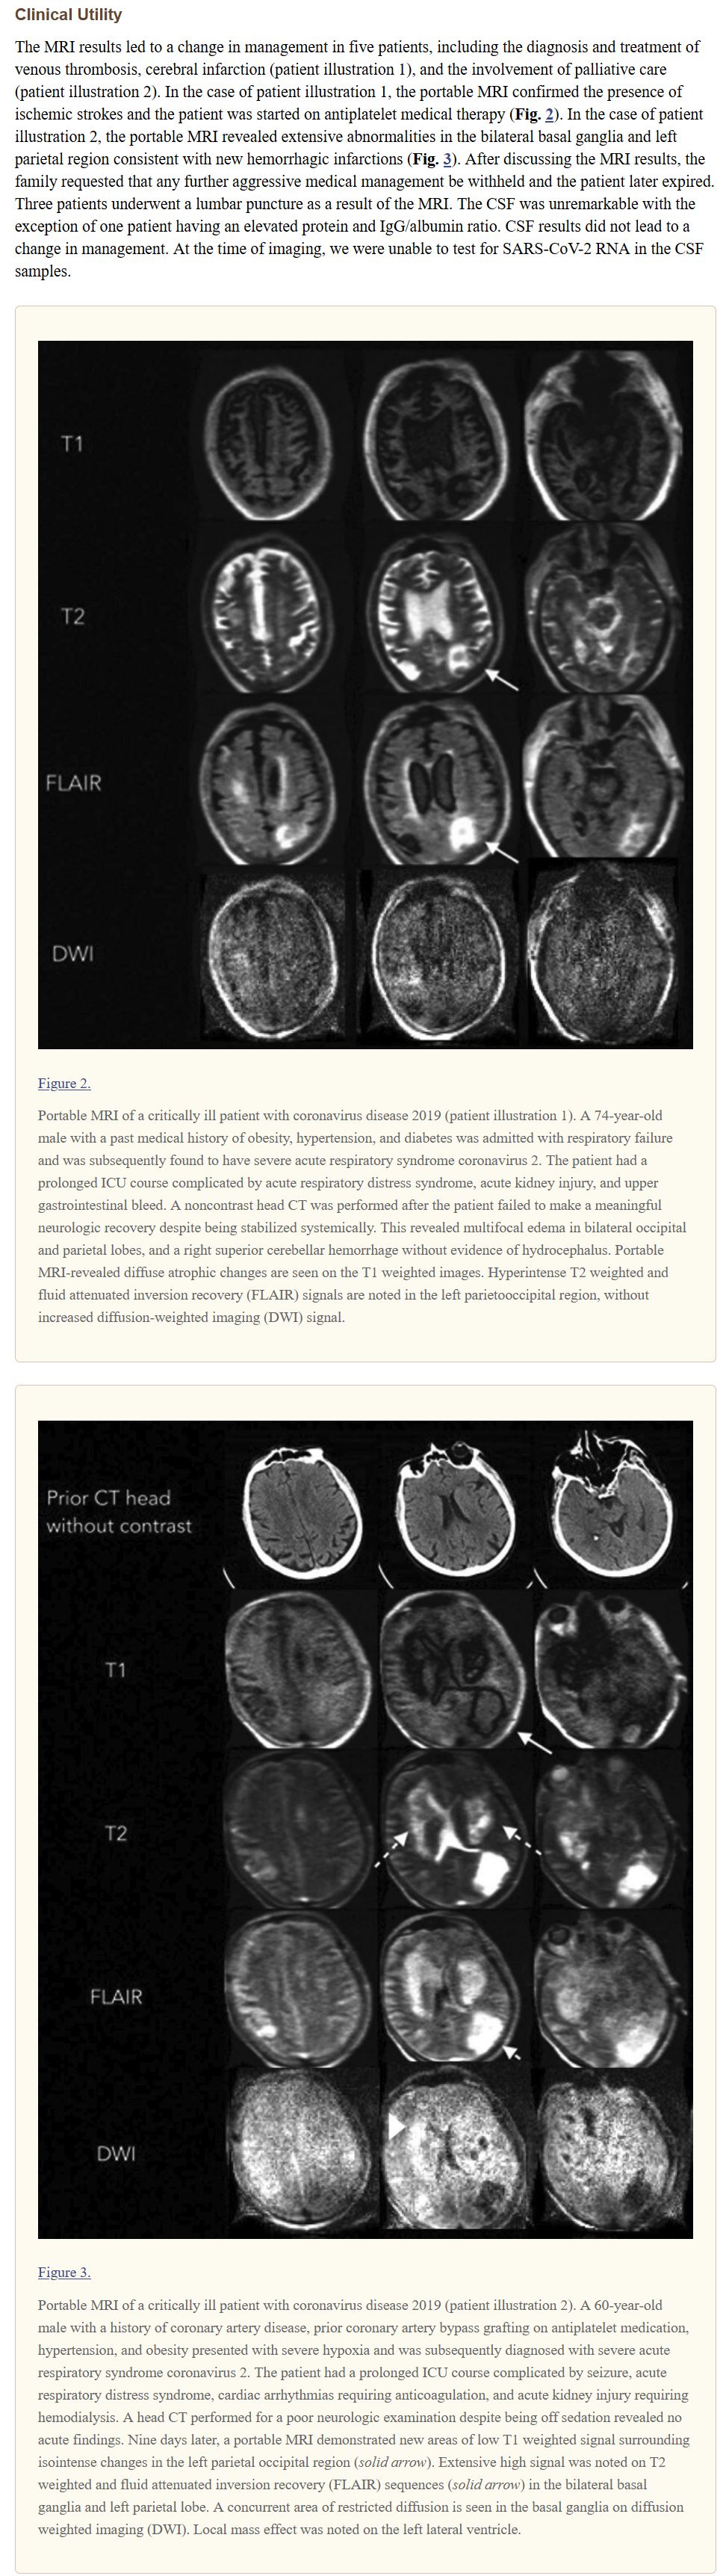

https://hyperfine.io/product/ https://www.ncbi.nlm.nih.gov/pmc/articles/PMC7769347/ https://pubmed.ncbi.nlm.nih.gov/32897296/ https://youtu.be/hpCLgcn_6kw https://youtu.be/j562iFvj-SM https://youtu.be/9kdmlZ3SnmE https://youtu.be/Z4cHc5AD5ac 현재는 대당 6천만원 정도라고 FDA 승인도 받았습니다. 기존 MRI보다 해상도가 낮아 완전 대체는 안 되지만, 소형이고, 일반 엘리베이터로도 이동이 가능한 크기고, 태블릿으로 조작 가능하고, 자석이 0.064T 정도라 별도의 보호 조치가 필요하지 않고, 일반 전기 아웃렛;콘센트 사용 가능하다고 합니다. 코로나19 시대에는 격리 병실에서도 사용 가능한 것이 또 장점이라고. 주가는... 0